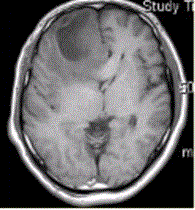

患者女,67岁,头痛伴呕吐1周。既往体健。MR表现如下图。临床拟诊为A.脑脓肿B.转移瘤C.成胶质胞瘤D.少枝胶质细胞瘤E.成髓细胞瘤

问题 患者女,67岁,头痛伴呕吐1周。既往体健。MR表现如下图。 临床拟诊为

选项 A.脑脓肿 B.转移瘤 C.成胶质胞瘤 D.少枝胶质细胞瘤 E.成髓细胞瘤

答案 C